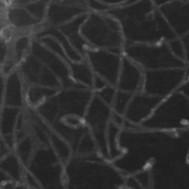

Semantic segmentation of blood vessels is an important task in medical image analysis, but its progress is often hindered by the scarcity of large annotated datasets and the poor generalization of models across different imaging modalities. A key aspect is the tendency of Convolutional Neural Networks (CNNs) to learn texture-based features, which limits their performance when applied to new domains with different visual characteristics. We hypothesize that leveraging geometric priors of vessel shapes, such as their tubular and branching nature, can lead to more robust and data-efficient models. To investigate this, we introduce VessShape, a methodology for generating large-scale 2D synthetic datasets designed to instill a shape bias in segmentation models. VessShape images contain procedurally generated tubular geometries combined with a wide variety of foreground and background textures, encouraging models to learn shape cues rather than textures. We demonstrate that a model pre-trained on VessShape images achieves strong few-shot segmentation performance on two real-world datasets from different domains, requiring only four to ten samples for fine-tuning. Furthermore, the model exhibits notable zero-shot capabilities, effectively segmenting vessels in unseen domains without any target-specific training. Our results indicate that pre-training with a strong shape bias can be an effective strategy to overcome data scarcity and improve model generalization in blood vessel segmentation.